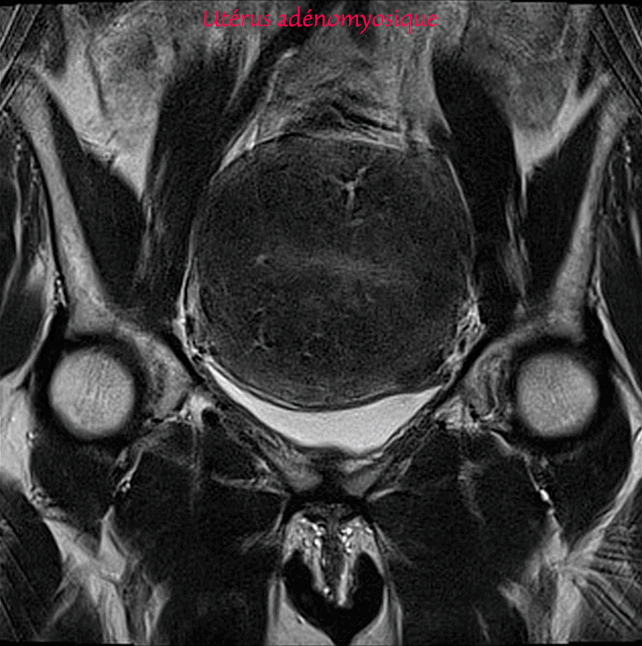

Utérus - Adénomyose florissante et petit myome sous séreux - IRM pelvienne

Images montrant l'aspect l'un en IRM de l'adénomyose à comparer à celui d'un myome